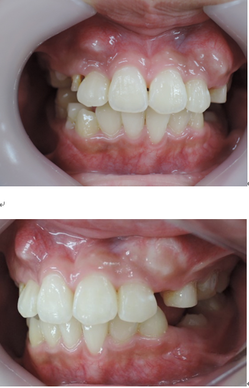

以下の上顎の症例では左右の第一小臼歯を抜かないと治療出来ないと説明があるはずです。しかし、当院での治療終了時には顎骨が拡大して綺麗に歯が並んでいます。

初診時 終了時

治療期間3年0か月で機能的で美しい咬み合わせが完成しました。

今回の症例は一般的に抜歯(第一小臼歯)が必要な症例ですが当院では非抜歯で治療する事が出来ました。

ただし、どんな症例でも非抜歯で治療できる訳ではありません。